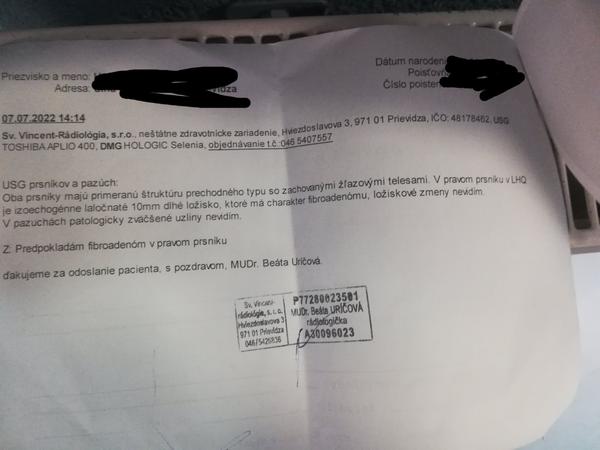

bola som na sone s hrčkami a dr. mi povedala, že sa pravdepodobne jedná o fibroadenóm. Ja mám ale hrčky dve vedľa seba a v popise je iba jedna. Dnes som bola u svojho doktora ktorý povedal, že o nič nejde ale ja mám napriek tomu strach. Dr. v závere napísala, že PREDPOKLADÁ, že sa jedná o fibroadenóm... takže ani na 100 % to nie je.